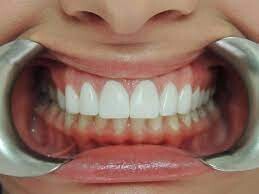

If you’re experiencing shrinking gums or tooth sensitivity while brushing and flossing your teeth, it could be due to receding gums. Also called gum or gingival recession, receding gums can’t grow back, but there are ways to catch the problem early and prevent your gums from getting worse. This article will discuss the causes, symptoms, treatment and how to prevent receding gums.

Many people wonder, 'can receding gums grow back?' But as we've mentioned, this isn't possible. Once your gum tissue has pulled back and away from your teeth, it’s gone for good. However, there are some options for managing gum recession, so see your dental professional for an evaluation to determine the cause of this problem. After an assessment, they can recommend the best course of treatment for your needs.